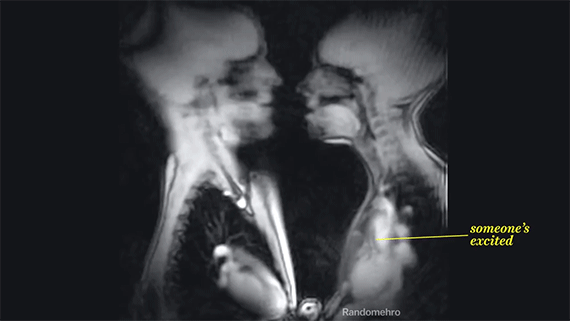

Το γύρο του Διαδικτύου κάνει ένα βίντεο που έχει φτιαχτεί από διαδοχικές μαγνητικές που ελήφθησαν την ώρα που ένα ζευγάρι έκανε σεξ.

Μέσα από αυτές δίνεται η δυνατότητα κανείς να... ρίξει μια ματιά στο εσωτερικό του ανθρώπινο σώματος και να διαπιστώσει το τι συμβαίνει σε αυτό την ώρα που βρίσκεται σε σεξουαλική διέγερση. Tα όργανα που πάλλονται, τις καρδιές που χτυπούν δυνατά, τις εισπνοές και τις εκπνοές κατά τη διάρκεια των φιλιών. Αυτό που προκαλεί εντύπωση είναι το πώς όλο το ανθρώπινο σώμα συμμετέχει στη διαδικασία και πόσο σύνθετη αυτή είναι.

Παρακάτω παρατίθεται μια κινούμενη εικόνα που δείχνει το τι συμβαίνει στο ανθρώπινο σώμα όταν ένας άνδρας και μια γυναίκα ανταλλάσσουν ένα καυτό γαλλικό φιλί.

Η ερωτική συνέρευση έγινε για τις ανάγκες της... επιστήμης και ο μαγνητικός στον οποίο ξάπλωσε το ζευγάρι δεν τους «κεραυνοβόλησε» με βλαβερή ακτινοβολία.